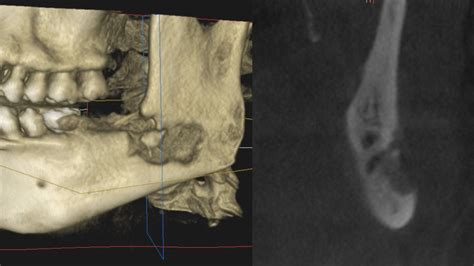

Aging and Bones

As we age, bones can become more brittle and prone to fractures. Osteoporosis, a condition characterized by low bone density, is a common concern for older adults. Some factors that contribute to bone loss with age include:

• Hormonal Changes: Menopause in women and andropause in men can lead to a decrease in bone density.

• Nutritional Deficiencies: Inadequate intake of calcium and vitamin D can weaken bones.

• Sedentary Lifestyle: Lack of physical activity can lead to bone loss.

Regular exercise, a balanced diet, and bone density tests can help maintain bone health as you age.